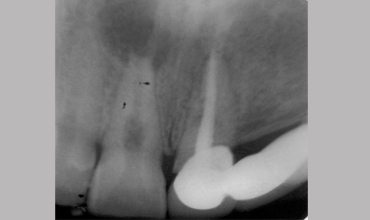

Management Of Internal Root Resorption In Maxillary Central Incisor Pre-operative Radiograph Removal Of Granulation Tissue With Ultra

Management Of Internal Root Resorption In Maxillary Central Incisor